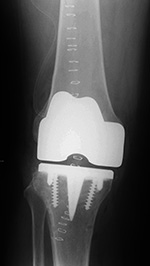

Cruciate retaining total knee arthroplasty (TKA)   Biomet Vanguard 360 Revision Knee System

Cruciate retaining TKA Cruciate retaining TKA Biomet Vanguard 360 knee revision Biomet Vanguard 360 knee revision

68 year-old woman treated for severe left knee osteoarthritis This replaced a loose prior total knee arthroplasty. The patellar button was left in place. A surgical drain is in place, and there is subcutaneous gas from the recent surgery.